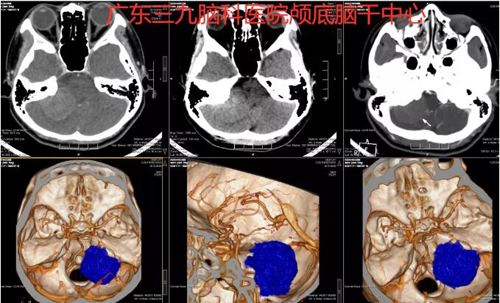

图1:术前CTA示右侧桥小脑角区团块状占位性病变内示少许小血管影走行,边缘示多发小血管环绕贴边走行,与右侧椎动脉V4段关系密切。

图2:术前MR示右侧桥小脑角区示一团块状占位性病变,呈稍长T1等T2异常信号影,FLAIR序列呈等信号,其内示斑片状短T2异常信号影,增强后呈明显异常强化影,大小约为3.9cm×2.7cm×4.4cm,增强后邻近硬脑膜增厚、强化,示脑膜尾征,右侧桥臂、右侧小脑半球受压,四脑室受压变窄。